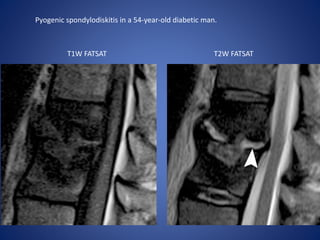

Pyogenic spondylodiskitis in a 54-year-old diabetic man.

T1W FATSAT T2W FATSAT

Pyogenic Spondylodiskitis Classic imagingfindings include a narrowed disk space with destruction of the neighboring vertebral endplates. Spine infection usually begins in the anterior aspect of the vertebral body because of its rich blood supply and subsequently extends through the disk to neighboring vertebral bodies. MRI shows decreased T1 signal intensity and increased T2 signal intensity in the affected vertebral endplates and disk. Post contrast images at an early stage of the disease process include enhancement of the disk and along the vertebral endplates; at a later stage, enhancement is accompanied by progressive destruction of the vertebral body.

Pyogenic spondylodiskitis ina 54-year-old diabetic man. T1W FATSAT T2W FATSAT

• #36 (a, b) Sagittal T1-weighted (a) and T2-weighted fat-suppressed (b) MR images demonstrate endplate-centered bone marrow edema with high signal intensity in the disk (arrowhead in b).

• #37 …..enhancement in the disk. Percutaneous aspiration of the disk contents yielded S aureus.